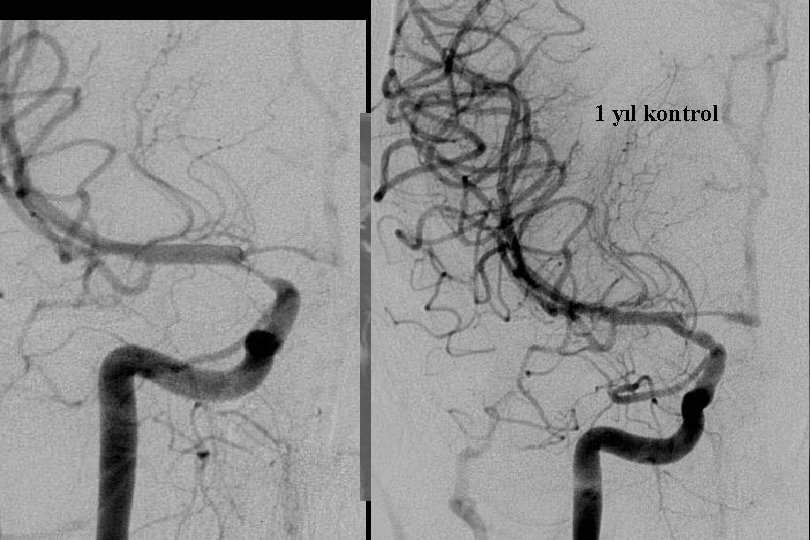

3 yıl kontrol

2. Yıl kontrol

1 yıl kontrol